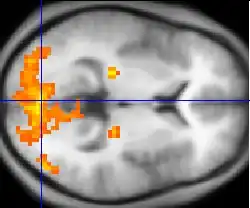

The varying techniques of imaging-based testing search for different signs of intelligence. The types of intelligence analyzed in this review were fluid intelligence (Gf), general intelligence (g), and crystallized intelligence (Gc). Early studies utilized information from patients with brain damage, noticing changes in intelligence scores that correlated to certain regions of the brain. As imaging technology has improved, so has the ability for deeper neuro-analysis. MRI studies have found that the volume of gray matter correlates to intelligence, providing evidence for generalizations made regarding brain/head-size and intelligence. Additionally, PET and fMRI studies have revealed more information regarding the functionality of certain regions of the brain.

By recording and interpreting the brain activity of subjects as they complete a variety of tasks, researchers are able to draw connections between the types of task (and thus, the type of intelligence) that calls on particular areas of the brain. Knowing how parts of the brain are utilized may reveal more information about the structure and hierarchy used in neural development. It also may provide interesting information regarding the pathways of neural signals as they navigate the nervous system. Image-based testing may allow researchers to discover why certain neurons are connected, if they are indeed aligned in a purposeful manner and consequently, how to repair such pathways when they are damaged.[2]

The lateral prefrontal cortex is a region of interest because those who have injuries to that part of the brain often have issues with common, everyday tasks such as planning their day. The LPFC is thought to be important for "cognitive control capacity," which can be used to predict future outcomes such as success in school and the workplace. It was found by van den Heuvel et al. that higher intelligence individuals employ more efficient whole-brain network organization. This had led to the thought that cognitive control capacity may be supported by these whole-brain network properties. The 2012 study used a theoretic approach to neuroimage data known as global brain connectivity (GBC) or weighted degree centrality. GBC let the researches look closely at specific regions and their range of connectivity. It was then possible to examine each region's role in human cognitive control and intelligence. The study used fMRI to acquire data and examine each region's connectivity.[11]